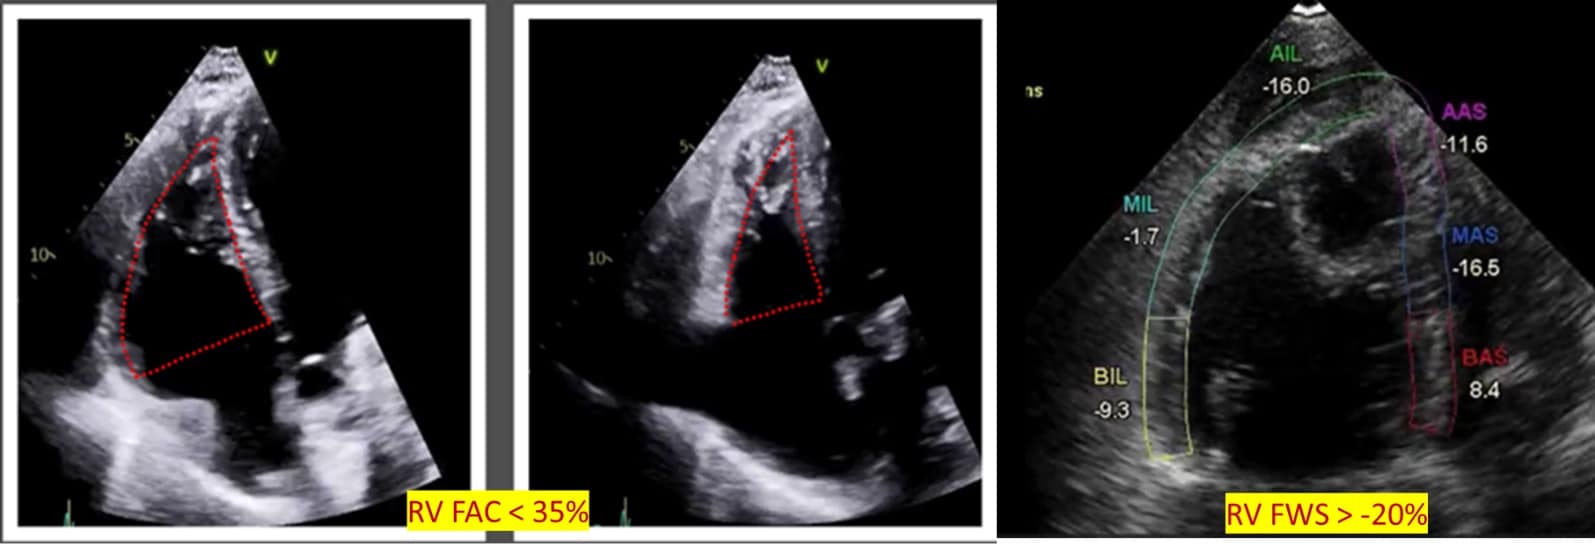

Overall, RV systolic function can be assessed using RV FAC and RIMP. FAC is measured in an A4C or RV-focused view, the percentage change of RV area at the end of systole from the end of diastole. Importantly, it is not angle-dependent and encompasses both radial and longitudinal function with FAC <35% considered abnormal.15 (Figure 5) RIMP or Tei index, obtained with Doppler at lateral annulus or pulsed wave Doppler at the tricuspid valve, is the ratio of time spent during the non-ejection time and, importantly, independent of the RV’s geometry. Time spent in non-ejection time increases with failure in RV dysfunction. Serial measurements can be used in prognostication of pulmonary hypertension and require a regular R-R interval for accurate assessment, but its utility is limited in critically ill patients.10,16

RVFW strain assesses RV systolic function using speckle tracking to measure the degree of deformation with values less negative than -20% considered abnormal. It is increasingly being used in the assessment of RV in critically ill patients.10,17,18 (Figure 5)

Figure 5: Global right ventricular systolic function.

RV = right ventricle, FAC = fractional area change, FWS = free wall strain